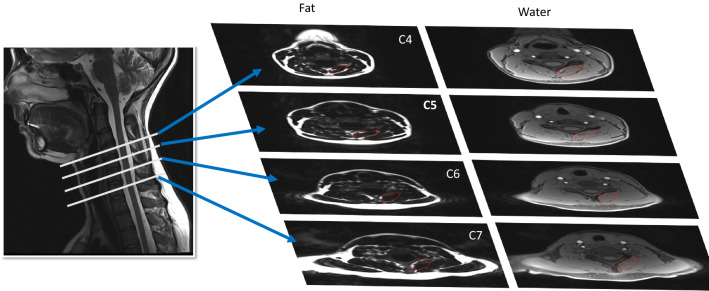

Each participant received MRI of their deep cervical extensors from C4 through C7 (Fig. 2), using a 3.0 T scanner with a 64-channel head/neck coil (Siemens, Munich Germany). Specifics of the fat/water MRI were as follows: dual-echo gradient-echo sequence (2-point Dixon), TR = 7.05 ms, TE1 = 2.46 ms, TE2 = 3.69 ms, flip angle = 12°, bandwidth = 510 Hz/pixel, FOV = 190 × 320 mm2, slab oversampling of 20% with 40 partitions to prevent aliasing in the anterior–posterior direction, in-plane resolution = 0.7 × 0.7 mm2, slice thickness = 3.0 mm3, number of averages = 6, acquisition time = 4 min 5s14. This fat/water sequence has been validated in animal models15.

Figure 2.

Fat/Water MRI of the deep cervical extensors from C4 through C7.